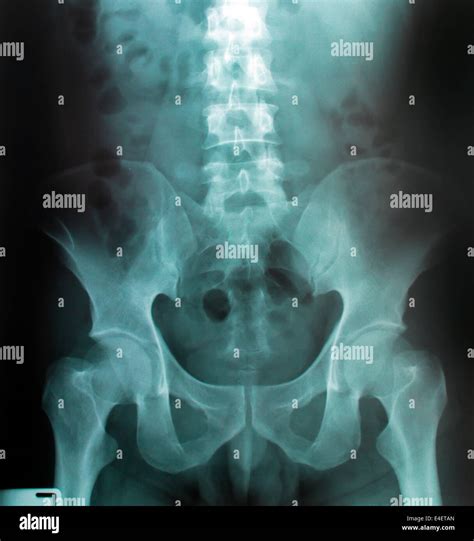

Normal Hip X Rays are a type of radiographic imaging used to visualize the hip joint and surrounding structures. This non-invasive procedure helps diagnose a wide range of conditions, including fractures, dislocations, arthritis, and developmental issues. The hip joint is a complex structure composed of the femoral head, acetabulum, and supporting ligaments and muscles. Normal Hip X Rays provide a clear view of these components, aiding in accurate diagnosis and treatment planning.

• Imaging: The radiographer positions the X-ray machine over the hip area and takes multiple images from different angles. These views typically include an anteroposterior (AP) view, which shows the front of the hip, and a lateral view, which shows the side of the hip.

Interpreting Normal Hip X Rays requires a trained eye and a thorough understanding of hip anatomy. Radiologists look for specific features and measurements to determine the health of the hip joint. Key areas of focus include:

• Joint Space: The space between the femoral head and the acetabulum should be uniform and well-defined. Narrowing of this space can indicate arthritis or other degenerative conditions.

• Alignment: Proper alignment of the femoral head within the acetabulum is crucial. Misalignment can suggest dislocations, fractures, or developmental issues.